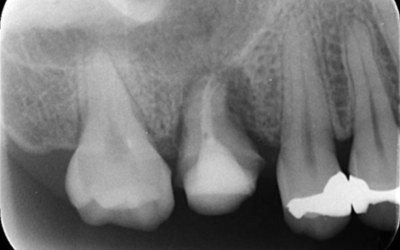

初診時デンタルX線写真

初診時デンタルX線写真とCT画像。

根管外に不透過像とそれを取り囲む透過像を認める。

コアを除去すると、分岐部へつながるパーフォレーションを認めた。

これが排膿の原因であったため、保存は困難と判断した。